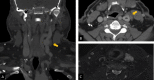

This paper reports a case of an internal jugular venous malformation (IJVM) and route of treatment in a patient with limited symptoms. After history and imaging studies, a determination of surgical excision was made to rule out possible malignancy and future problems such as thrombosis. The mass was resected, and part of the IJVM was ligated. The mass had no identifiable malignancy, and the patient recovered fully with no complications. The paper highlights the importance of identifying venous malformations and highlights the reasoning behind the course of action.